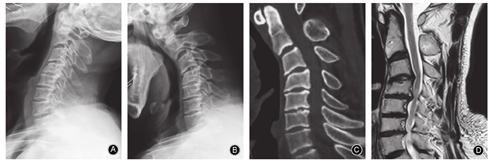

依据影像学特点将脊髓型颈椎病分成简单和复杂两类:颈椎退变轻(1~2个节段)的单纯椎间盘突出、颈椎曲度好、椎间隙基本正常确定为简单影像学特点的颈椎病;而把多节段(≥3节段)椎间盘突出和较大骨赘形成、椎间隙严重狭窄、巨大椎间盘突出和钙化、黄韧带肥厚钙化、椎间不稳、后凸畸形、后纵韧带骨化等视为复杂影像学特点的颈椎病(图1)。尤其是对多节段脊髓型颈椎病患者,其影像学复杂程度不仅反映在致压因素的数量、脊髓受压程度的轻重、受压范围的大小,也反映在解除致压因素的难易程度和手术方式选择,这对临床选择手术入路及减压方式有重要的指导意义[11,12]。